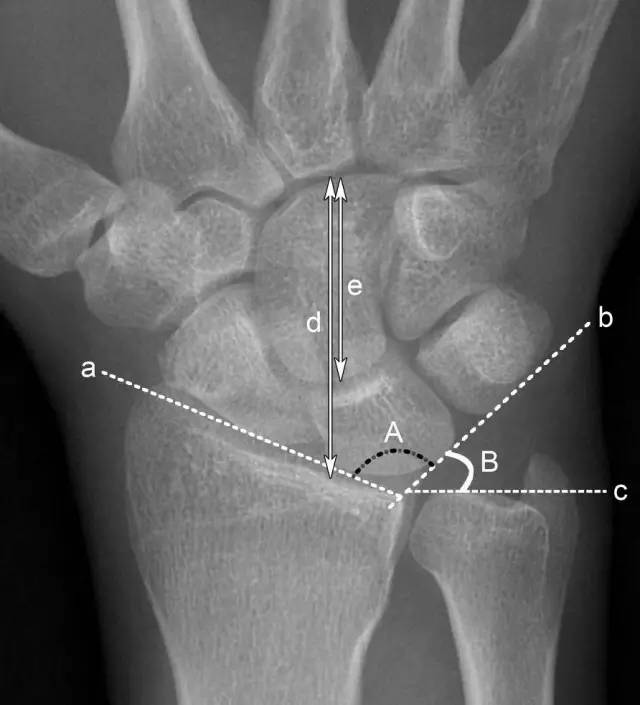

A. 腕骨角:约130°,腕关节骨折、脱位时此角增大。

B.尺腕角:正常为21°-51°,若此角度改变,提示腕骨骨折或腕关节脱位。

a.舟骨、月骨切线 b. 月骨三角骨切线 c.尺骨远端关节面切线 d.腕骨总高度 e.头状骨长度 A.腕骨角 B.尺腕角